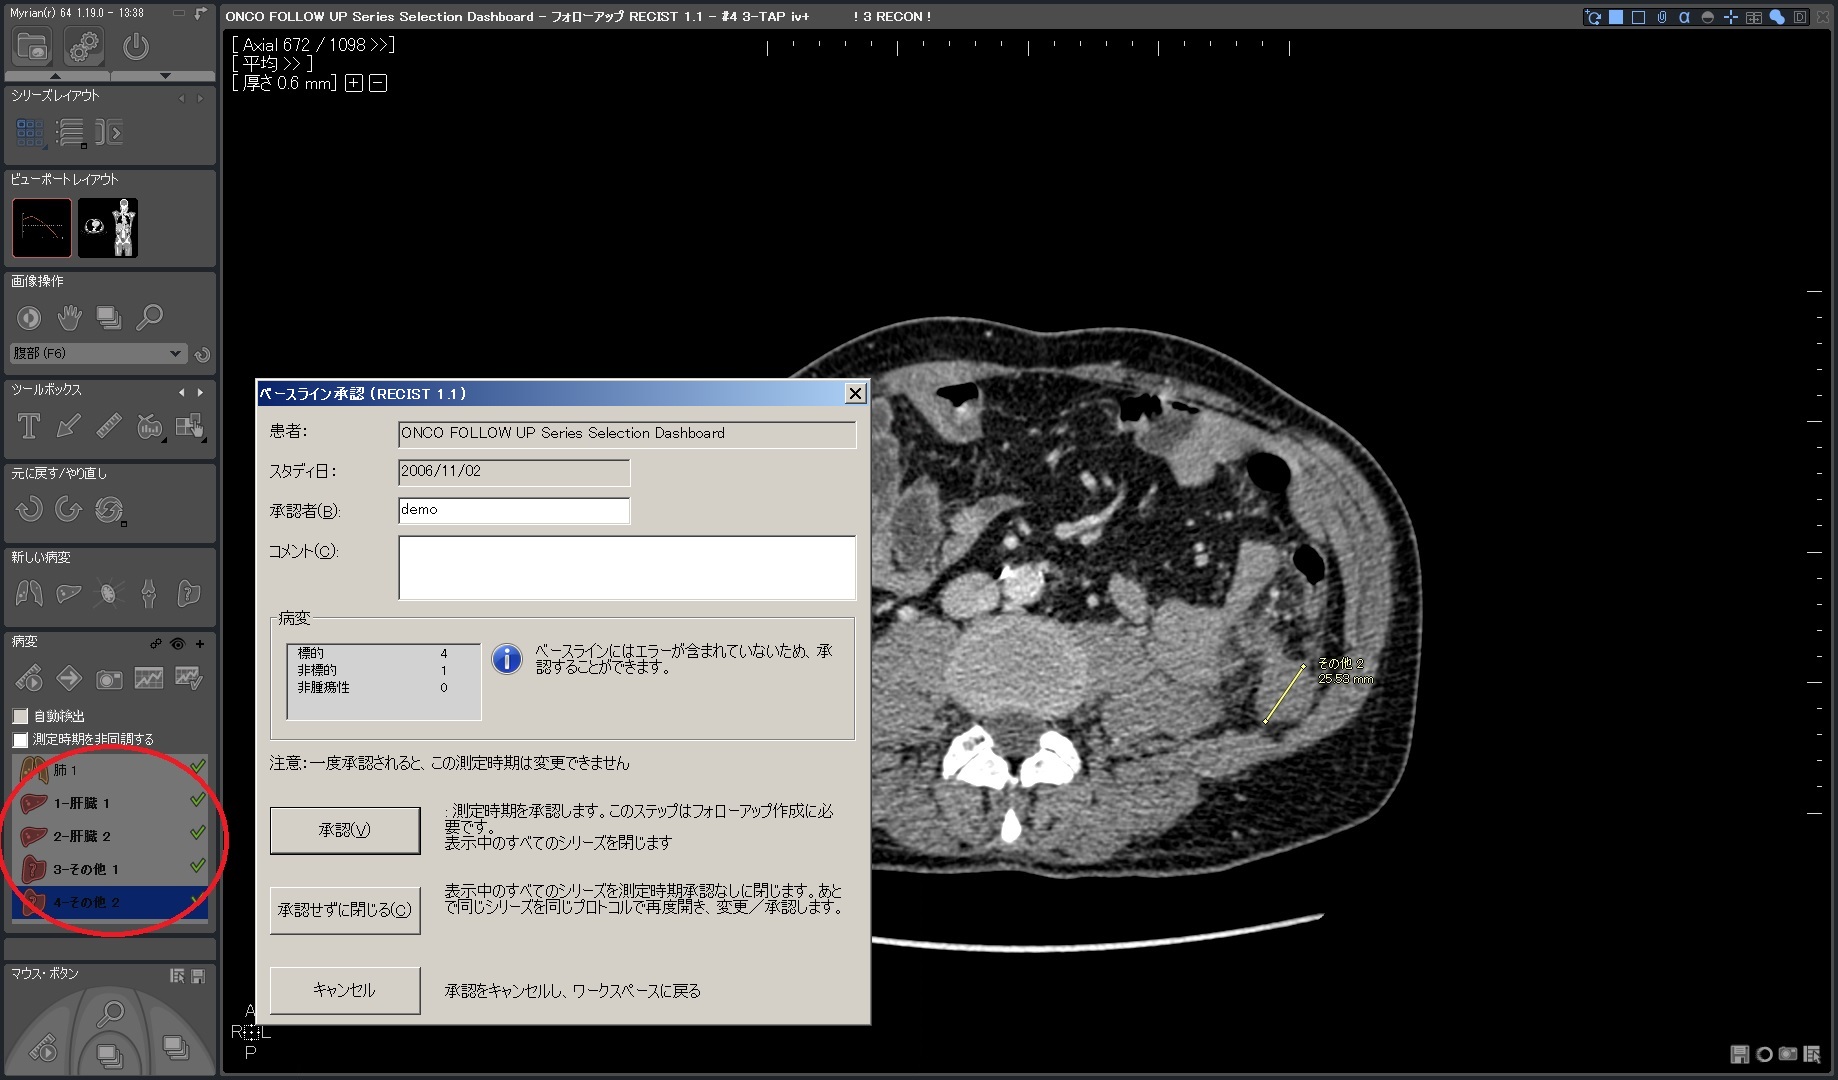

| 1.ベースライン作成 |  |

| 2.ターゲット/非ターゲット 各種ROIを計測 、承認 |